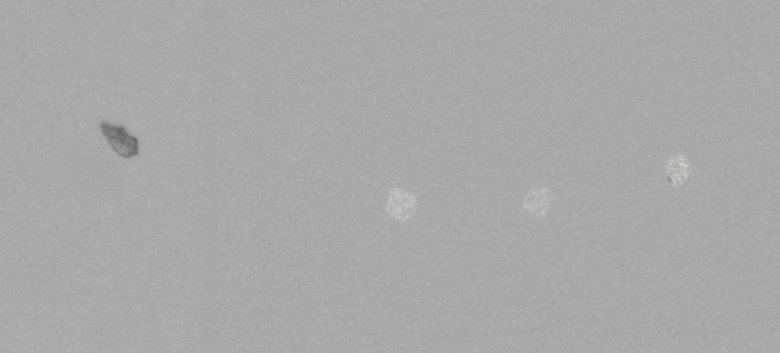

下圖為樣品顆粒在顯微計數(shù)法不溶性微粒儀下的顆粒形貌: